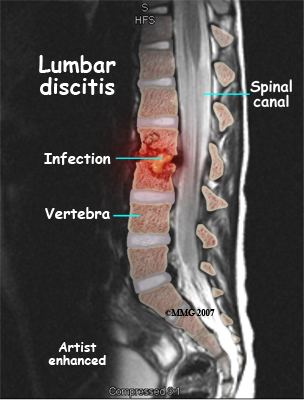

Discitis and vertebral osteomyelitis are rare in children. When a disc becomes inflamed and possibly infected, the condition is called discitis. If the vertebral bone becomes infected, the condition is called vertebral osteomyelitis.

Common symptoms of these conditions include refusal to crawl, sit, or walk and complaints of back pain. A limp and forward bending while placing the hands on the thighs for support are also common signs.

With discitis, the disc will appear narrowed on an X-ray or an MRI. Discitis usually occurs in children less than five years old.

Vertebral osteomyelitis tends to affect older children and adolescents. The vertebral bone and surrounding tissue including the disc can become infected. On X-ray or MRI the bone and/or tissue can show destruction. Fever of 102 degrees Fahrenheit or 39 degrees Celsius or greater is common in vertebral osteomyelitis.

Both discitis and vertebral osteomyelitis are treated with rest, as well as oral and IV antibiotics. A brace to support the spine may be suggested. With osteomyelitis surgery may be necessary to clean out the infection and/or to stabilize the spine.